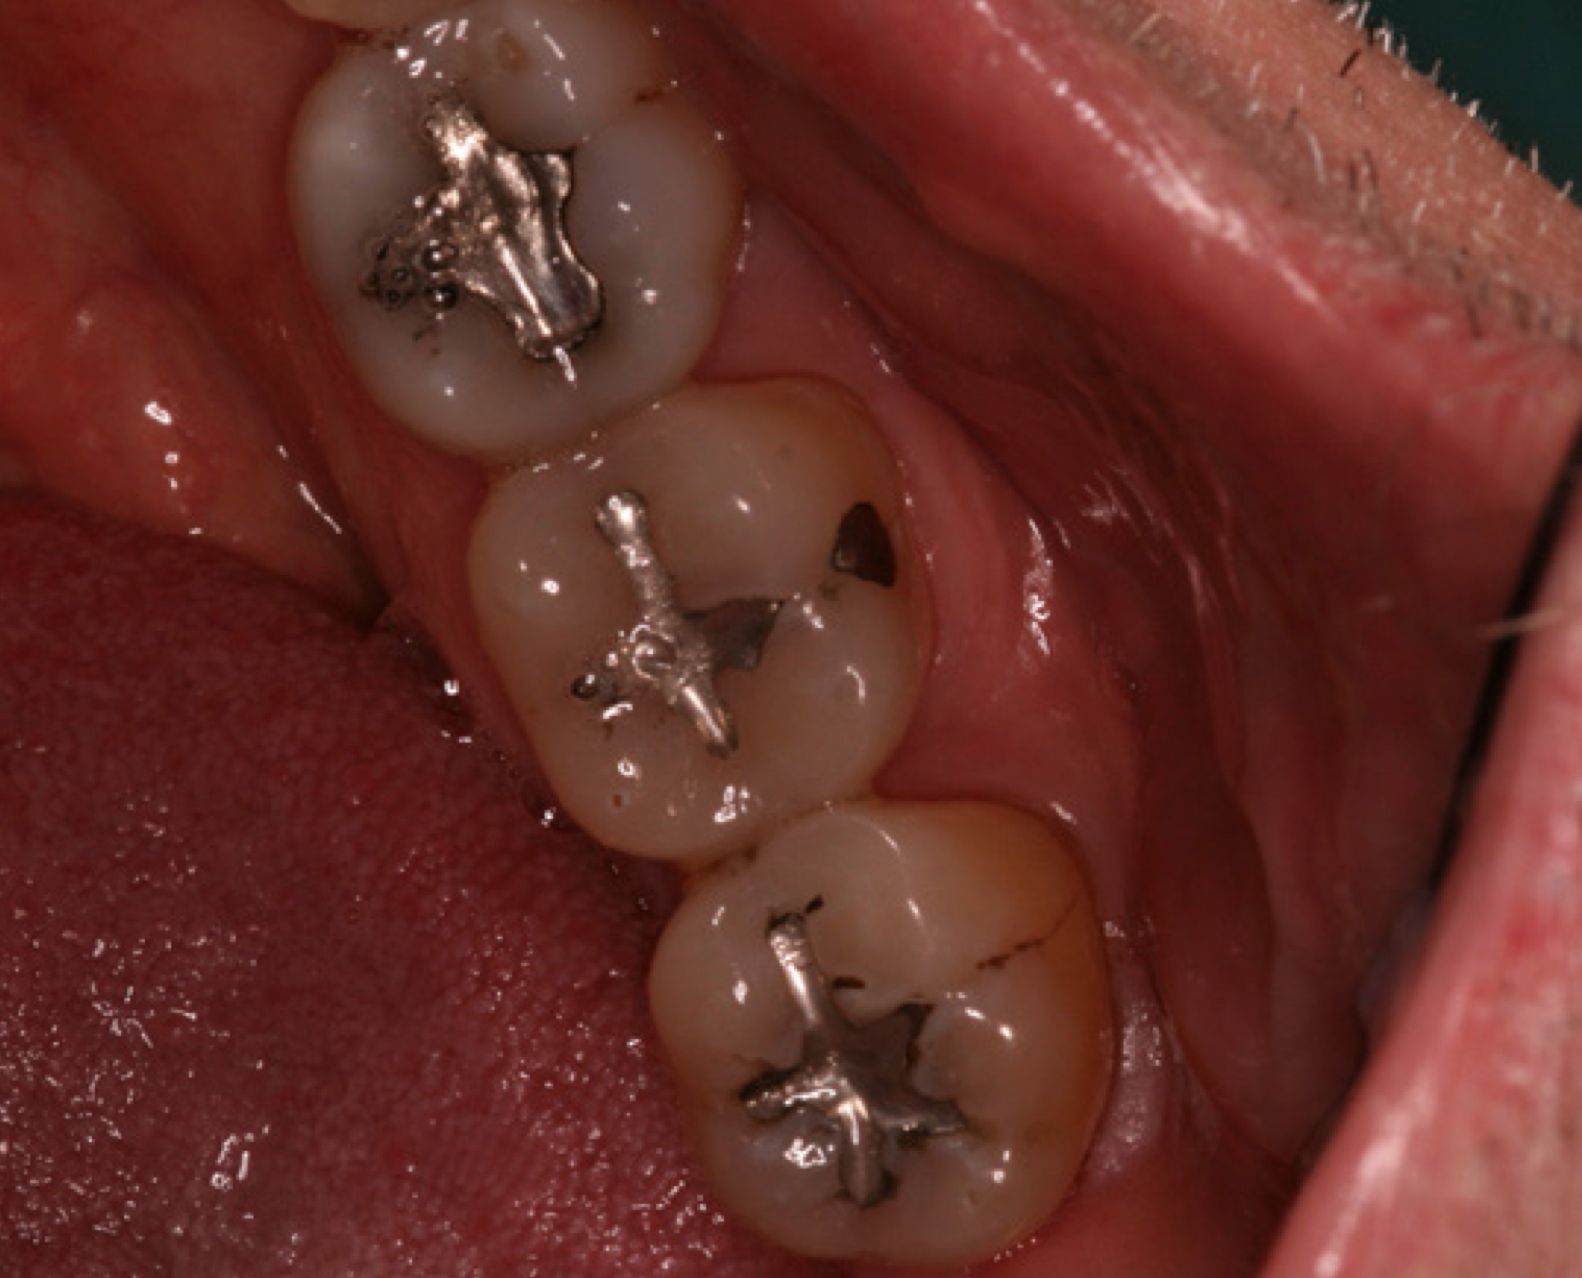

Amalgam materials – The first reported use of amalgam as a restorative material dates back to 659 AD in China. Amalgam is a substance that combines two or more different metals, usually silver, copper, zinc, and tin to form an alloy. This alloy is combined with mercury to make dental amalgam. Various groups have tried to have amalgam banned because of the toxicity of mercury in certain situations. Studies continue to show amalgam as a safe, affordable, durable, restorative material, backed by the American Dental Association and governmental agencies. Amalgam is still a common material used for dental restorations today (Figure 1).

Advantages of amalgam include its durability and long lasting restorations, ease of use in hard to reach areas, or in areas where isolation of fluids is a problem. It is time efficient, which is important when children are uncooperative. Disadvantages of amalgam include its color, concerns about mercury content, and the possible need for the removal of healthy tooth structure for mechanical retention. (For more information on mercury refer to the ADAA course Mercury in Dentistry - The Facts.)